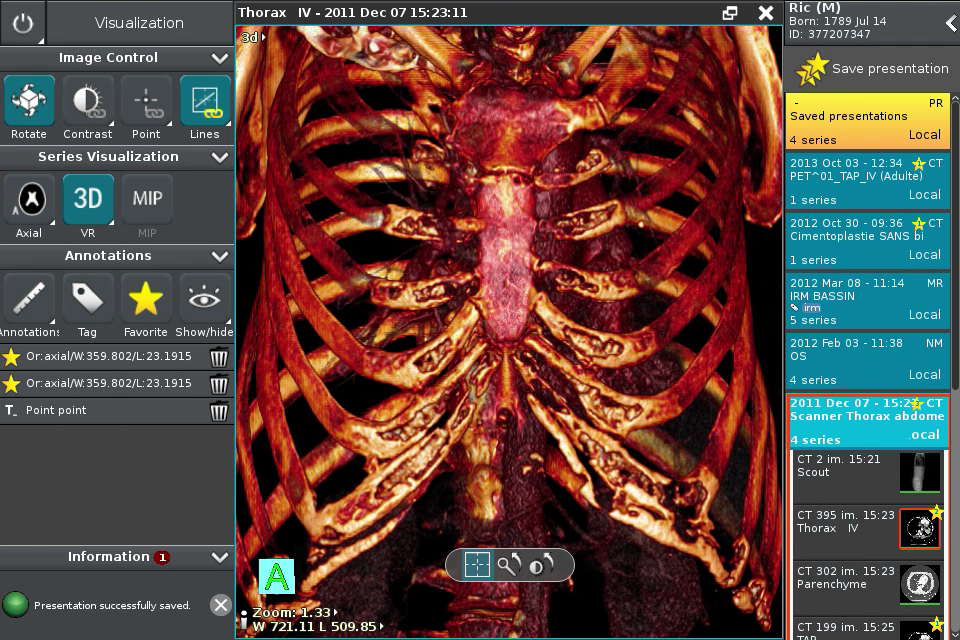

Anywhere Streaming is a DICOM visualization client that connects to Anywhere Server. It provide standard medical image navigation tools surch as : slicing, windowing, MPR, 3D VR, MIP, oblique ...

All standard medical image modalities are supported : MR, RX, CT, PET, NM, MG, US ...

Screenshots